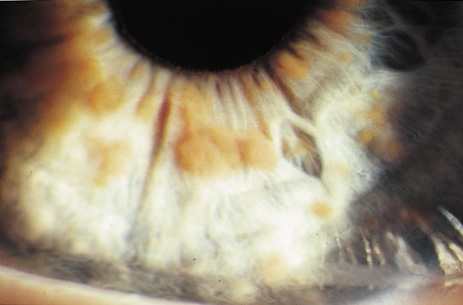

Lisch nodules are hamartomas (a tumor involving only those tissue elements normally found at the involved site) of the iris pigment epithelium. They are dome-shaped discrete lesions, are typically light brown in color, and may also be found in the angle.38 Lisch nodules appear earlier (33% at 2.5 years, 50% at 5 years of age)39 than neurofibromas. They are benign and can help to confirm diagnosis in children who may have café au lait spots as the only other clinical finding. Lisch nodules are present in nearly all adults with NF139,40 but are rare in NF2 (Fig. 3).41,42 Diffuse nodular iris nevi (also known as iris mamillations) should not be confused with Lisch nodules. Its clinical significance is not well established.43,44

Fig. 3. Neurofibromatosis type 1: Lisch nodules. These are hamartomas of the iris pigment epithelium. Lisch nodules are present in nearly all adults with NF1,39,40 but are rare in NF2.41,42

2. At least two Lisch nodules (Fig. 3)